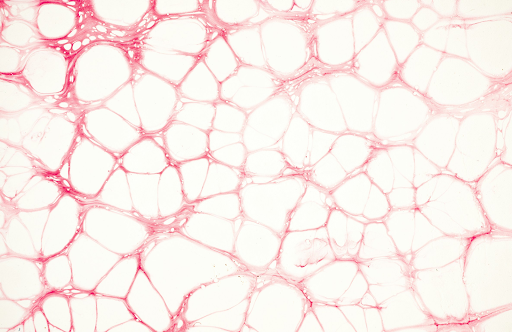

A microscopic view of broken capillaries

Broken capillaries (also known as telangiectasia) are tiny, dilated blood vessels that appear close to the skin’s surface, typically on the nose, cheeks, and chin. While they’re not harmful, they can be a cosmetic concern for many.